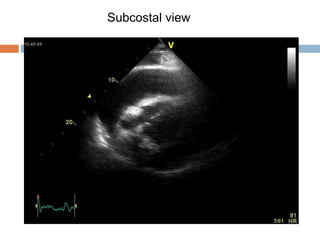

 2D and M-mode

 RV diastolic collapse

 RA collapse/inversion

 IVC plethora

 RV Diastolic Collapse

 Most commonly involves the RV outflow tract (more

compressible area of RV)

 Occurs in early diastole, immediately after closure of the

pulmonary valve, at the time of opening of the tricuspid valve

 When collapse extends form outflow tract to the body of the right

ventricle, this is evidence that intrapericardial pressure is

elevated more substantially

Circulation. 1977, 56: 774-9.

Subcostal view